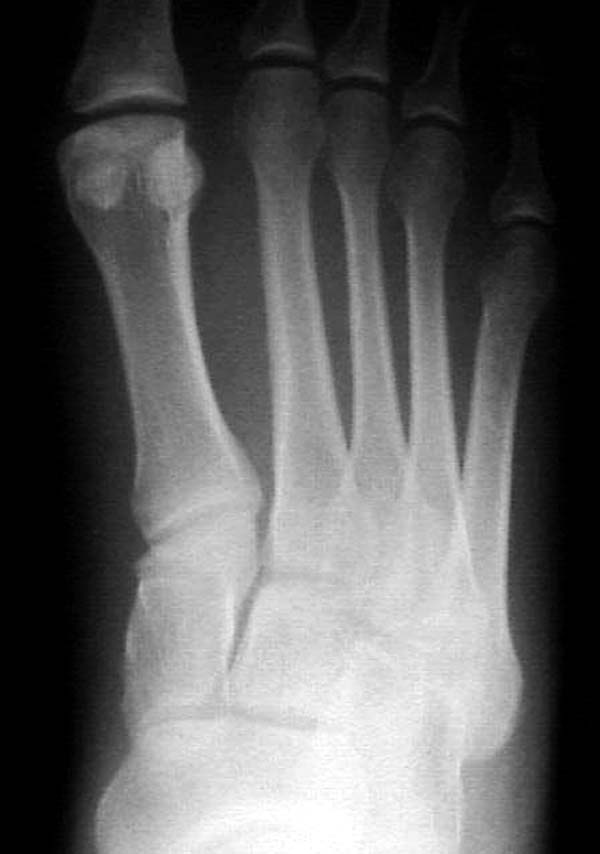

По снимкам нельзя исключить разрыв связки Лисфранка (связки между медиальной клиновидной костью и основанием второй плюсневой). Помогает в диагностике клиника (наличие изолированной гематомы на подошвенной поверхности стопы) и МРТ картина. Если связка повреждена - необходимо оперативное лечение.

По первому снимку, не видя больного, мог бы заподозрить перелом основания 3-й плюсневой кости. Поэтому избрал бы тактику консервативного лечения, как при переломе плюсневых костей без смещения!

Здесь КТ и сравнительные снимки стопы под нагрузкой.

Диагностировано повреждение медиальной и латеральной колонны.

Если оперативное лечение - как и каким доступом?